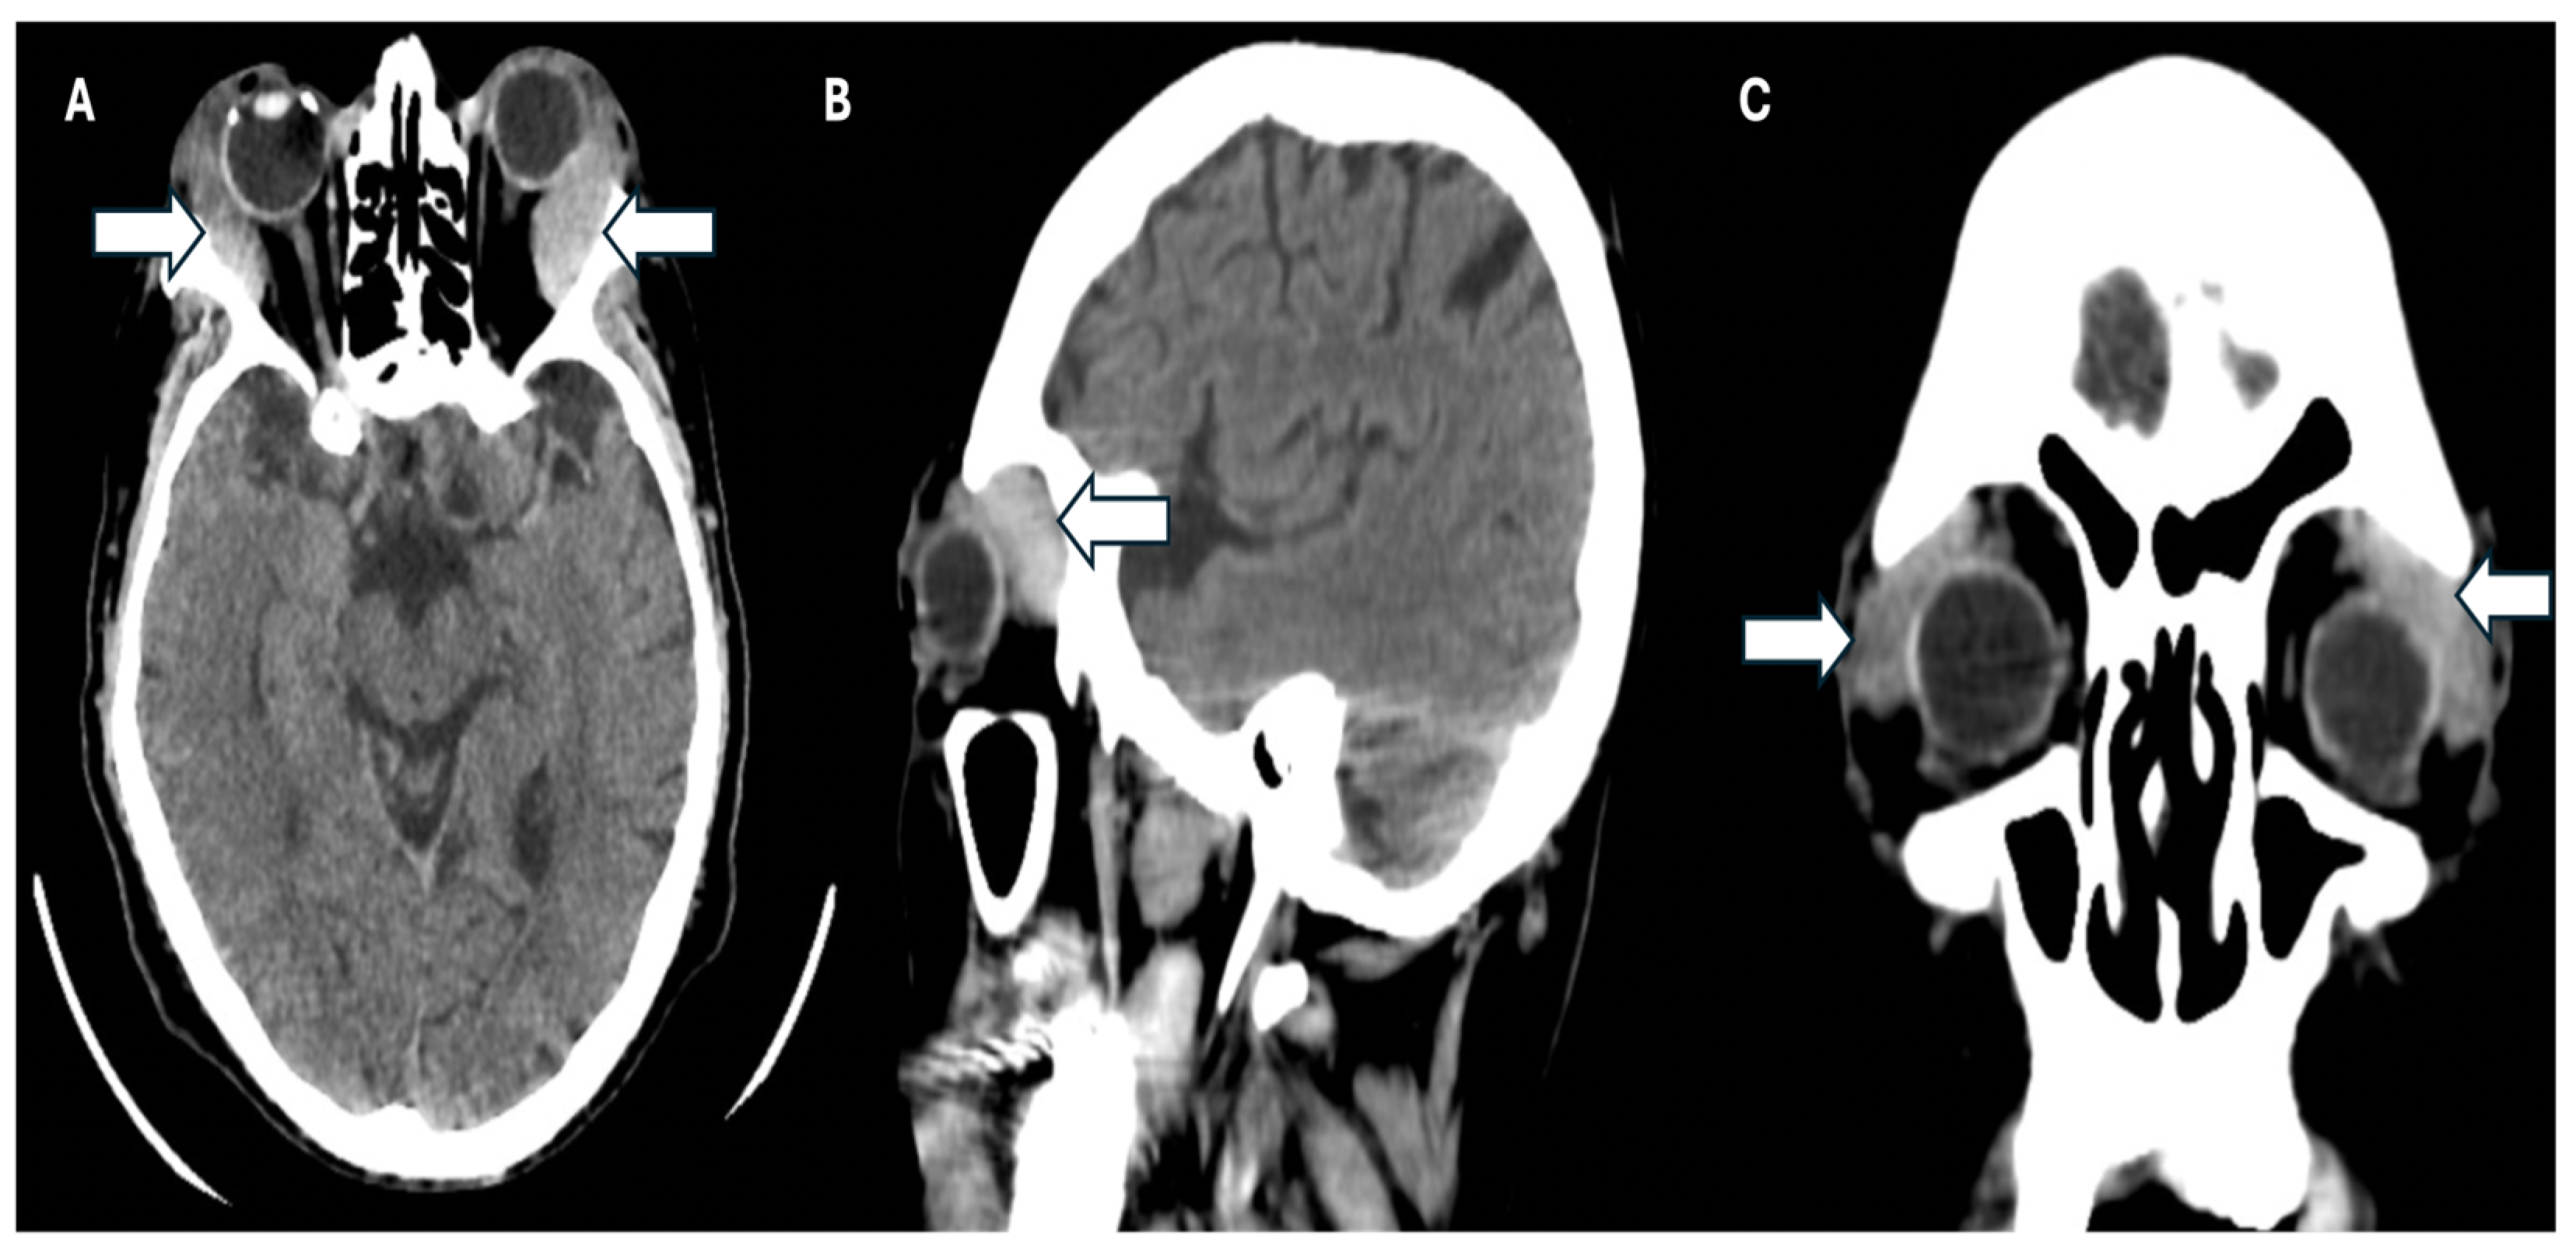

Simultaneously, a simple phase cranial computed axial tomography (CT) scan was requested to continue the approach. This revealed the presence of heterogeneous masses in the upper temporal sector of both orbits at the level of the lacrimal glands, and infiltration of the adjacent orbital tissue, causing bilateral proptosis. Additionally, there was evidence of bilateral maxillary sinusitis, with no indication of periorbital cellulitis (Figure 3 A-C).

Figure 3. CT scan of the patient. A: Axial plane, B: Sagittal, and C: Coronal plane where the arrows show infiltration of the adjacent orbital tissue, causing the patient’s bilateral proptosis.